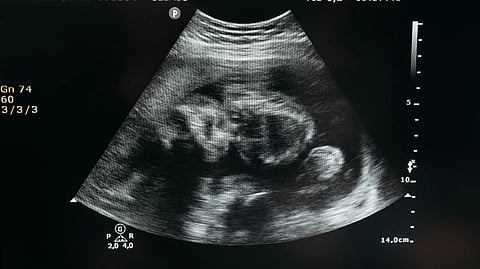

Ultrasound image showing a black and white sonogram of a fetus in the womb.

AI-enhanced fetal ultrasound at Mount Sinai helps doctors detect congenital heart defects earlier, improving care for babies and families.Pavel Danilyuk/ Pexels